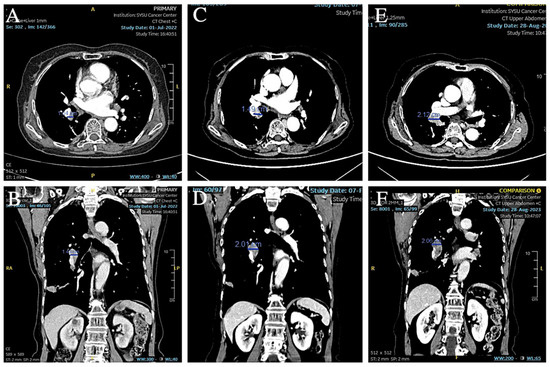

A 74-year-old female patient was referred to our hospital on 17 December 2020 due to an abnormality of the right lower lung detected on X-ray after a fall that injured her upper abdomen. She was never a smoker. Chest CT suggested that a nodule was seen in the dorsal segment of the lower lobe of the right lung, about 16 × 14 mm in size, with unclear borders, foliation, and short burrs at the margins, and significant enhancement was seen on enhancement scanning, which was adherent to the neighboring pleura (Figure 1A,B). No significantly enlarged lymph nodes in the hilar and mediastinal regions or larger lymph nodes with a short diameter of less than 1 cm (Figure 1C–F) were detected. No effusion was seen in the bilateral pleural cavity, and no thickening of the pleura was seen bilaterally. In addition, the cranial magnetic resonance and electron bronchoscopy did not reveal any obvious abnormality (PET-CT was not performed). On 23 December 2020, the patient underwent dorsal segmentectomy of the right lower lobe of the lung and mediastinal lymph node dissection. The histopathological report of the patient’s postoperative specimen showed heterogeneous cells arranged in nests, with little cytoplasm, high nuclear-to-pulp ratio, deep nuclear staining, and degeneration of individual nuclei accompanied by lamellar necrosis, which, combined with the immunohistochemical results, led to the diagnosis of a high-grade neuroendocrine carcinoma, consistent with small cell lung carcinoma. The five lymph nodes in the hilar and one in the mediastinal regions that were cleared intraoperatively showed no cancer metastasis, and the pathologic stage was pT2N0M0 IB.

Figure 1. (A,B) Preoperative CT showed a space-occupying lesion in the lower lobe of the right lung. (C,D) Preoperative CT showed hilar lymph nodes with a short diameter less than 1 cm. (E,F) Preoperative CT showed other lymph nodes in the mediastinal region.